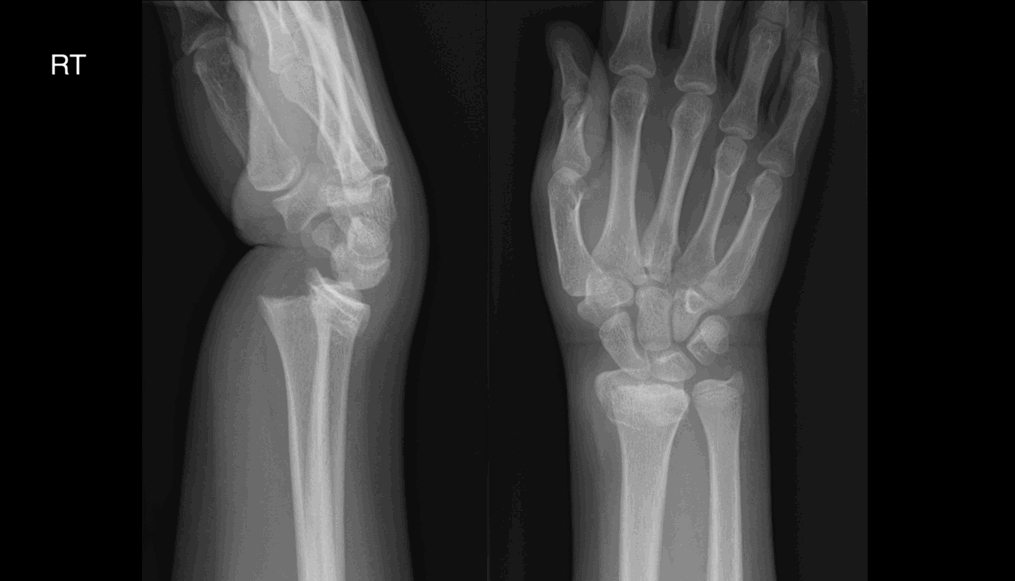

Age 14, male. Referral from ED. History: Painful wrist after falling off skateboard.

Findings:

Fracture through distal (growth plate of) radius

Dorsal displacement of distal radial epiphysis

Metaphysis intact

Diagnosis Salter Harris I fracture distal radius

Ulnar styloid fracture

| Sample answer | Answer type | Explanation of scoring allocation |

|

Distal radius fracture through the growth plate, with dorsal displacement. |

High scoring answer |

This answer would score highly because it is concise, well-structured and the candidate has made all the relevant observations including growth plate involvement. It is anatomically accurate with correct classification of the fracture. The report has been appropriately escalated. |

There is a displaced fracture of the distal radius with dorsal displacement (Colles type fracture). |

Mid-scoring answer |

This answer would not score so highly because the candidate has failed to recognise that the fracture involves the distal radial growth plate. |

Left radiocarpal dislocation No fracture |

Low scoring answer |

This answer has a low score because the candidate has misinterpreted the findings and made an incorrect diagnosis |